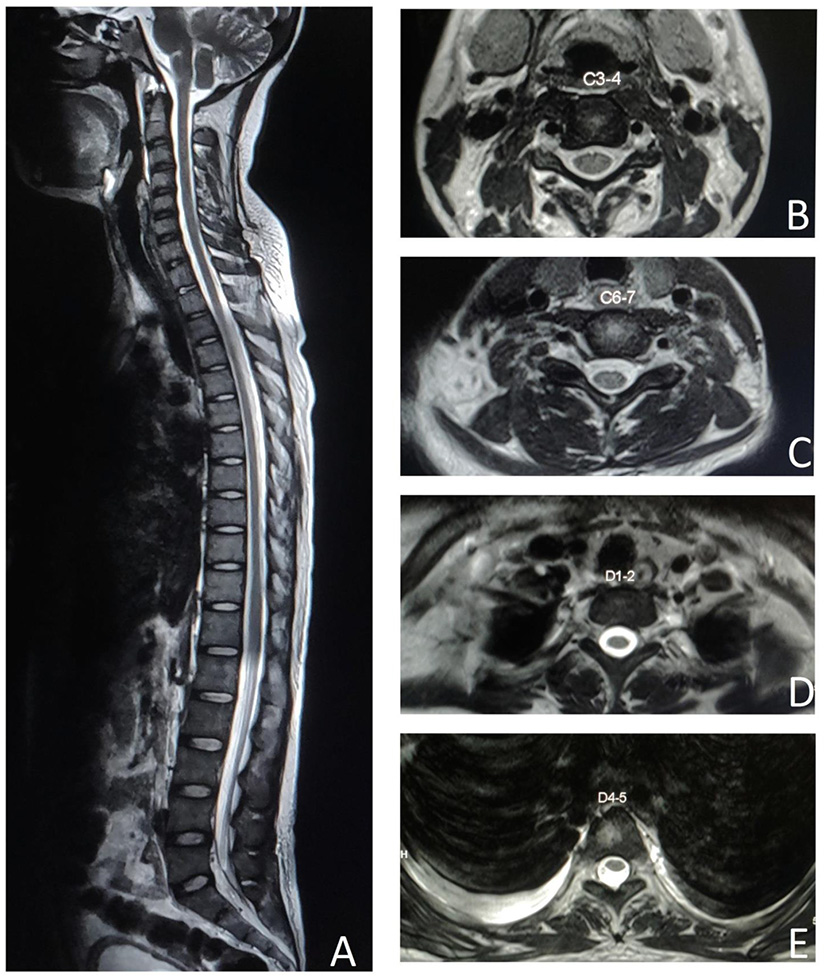

Illustrative case: A 45-year-old female had complaints of quadriparesis for last 7 days. It started as an acute retention of urine and paraparesis, followed by bilateral upper limbs weakness from the next day, without any sensory and cranial nerve symptoms. She also had history of oral ulcers, malar rash, alopecia, photosensitivity and symmetrical small joint pain and swelling for last 2.5 months along with low grade fever and pedal edema for last 1 month.

MRI spine didn't reveal any cord signal change on repeated imaging (Figure 2). Nerve conduction study showed acquired motor axonal polyradiculoneuropathy. CSF analysis had pleocytosis with mildly elevated protein. Biochemical investigations revealed ANA, anti-dsDNA, Rib-P, Sm, and RNP positivity with hypocomplementemia. There was presence of urinary RBC cast with macro-albuminuria on further searching for organ involvement. Patient denied permission for renal biopsy.

Figure 2

MRI spine T2 weighted image shows no spinal cord signal changes in the sagittal section (A), cervical axial sections at C3–4 (B), C6–7 (C), dorsal axial sections at D1–2 (D), and D4–5 (E).